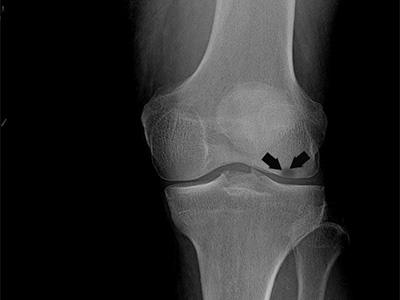

Knee Arthritis

Like other joints that carry your weight, your knees are at risk for "wear and tear" arthritis. The smooth articular cartilage (cushion) that helps your knee joint glide may wear thin. Generally, the pain of arthritis develops gradually, although sudden onset is also possible.

Meniscal Tear

Meniscal tear is the commonest knee injury in athletes, especially those involved in contact sports. A sudden bend or twist in your knee can cause the meniscus to tear. This is a traumatic meniscal tear.